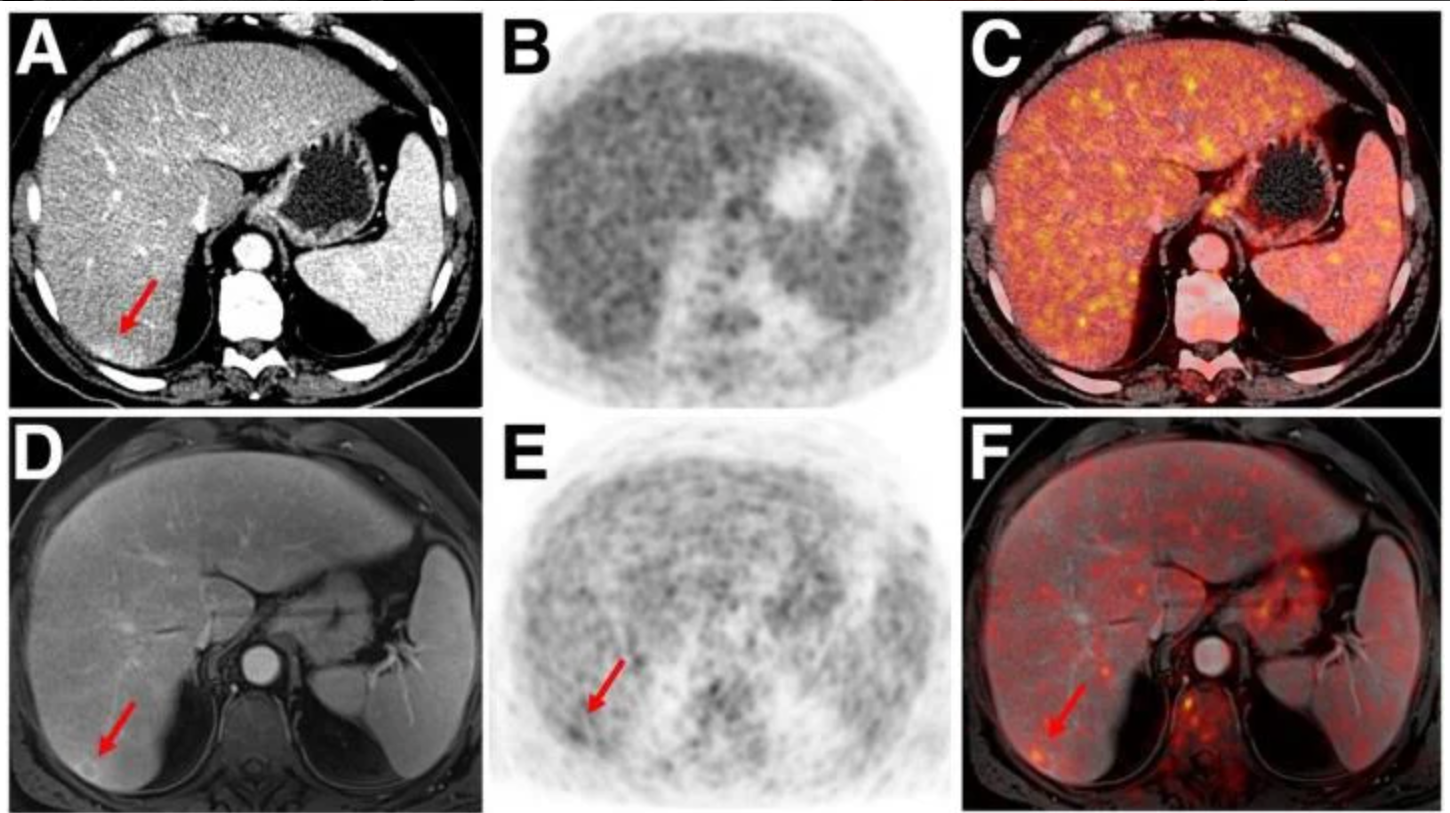

Brain Mri How To Read Mri Brain Scan Kenhub | ![]() Representative Pet Mri Images From The Patients No 2 A C No 5 Download Scientific Diagram | ![]() The Top 5 Of Mri In |